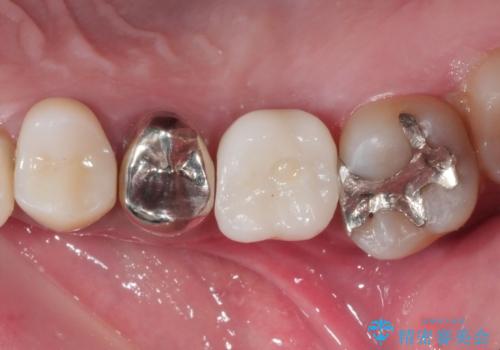

インプラント治療により問題無く奥歯で噛めるようになりましたが、奥歯の噛み合わせが強いためインプラント周囲の骨吸収や他の歯の破折等が起きる可能性があります。

夜間就寝時のマウスピース装着、定期的なメンテナンスでレントゲン、噛み合わせの確認は必須です。